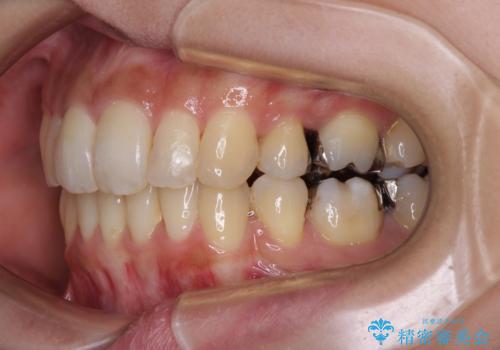

- 抜歯矯正の後戻りで前歯が突出してきていることを気にして来院された患者様です。

口元の突出感を改善するにあたり、抜歯矯正は行うことができないため、奥歯の後方移動とIPR(歯と歯の間を削る)により達成することとしました。

再度後戻りしたときに対応しやすいよう、インビザラインにて矯正治療を行うこととしました。